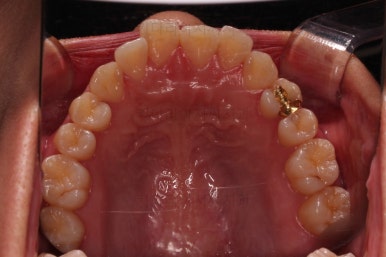

초진 시 입안의 모습입니다.

치열이 많이 삐뚠 것은 아니지만 앞니쪽이 삐뚤어 있고요. 아랫니 사이사이에 고루 틈새가 있네요.

윗니는 삐뚤고(공간부족), 아랫니는 틈새가 있다면(공간 과잉) 그 부조화는 부정교합을 의미합니다.

어금니 교합이 전반적으로 아랫니가 뒤로 빠져있는 교합이어서 맞물림이 좋지 못한 상태였어요.